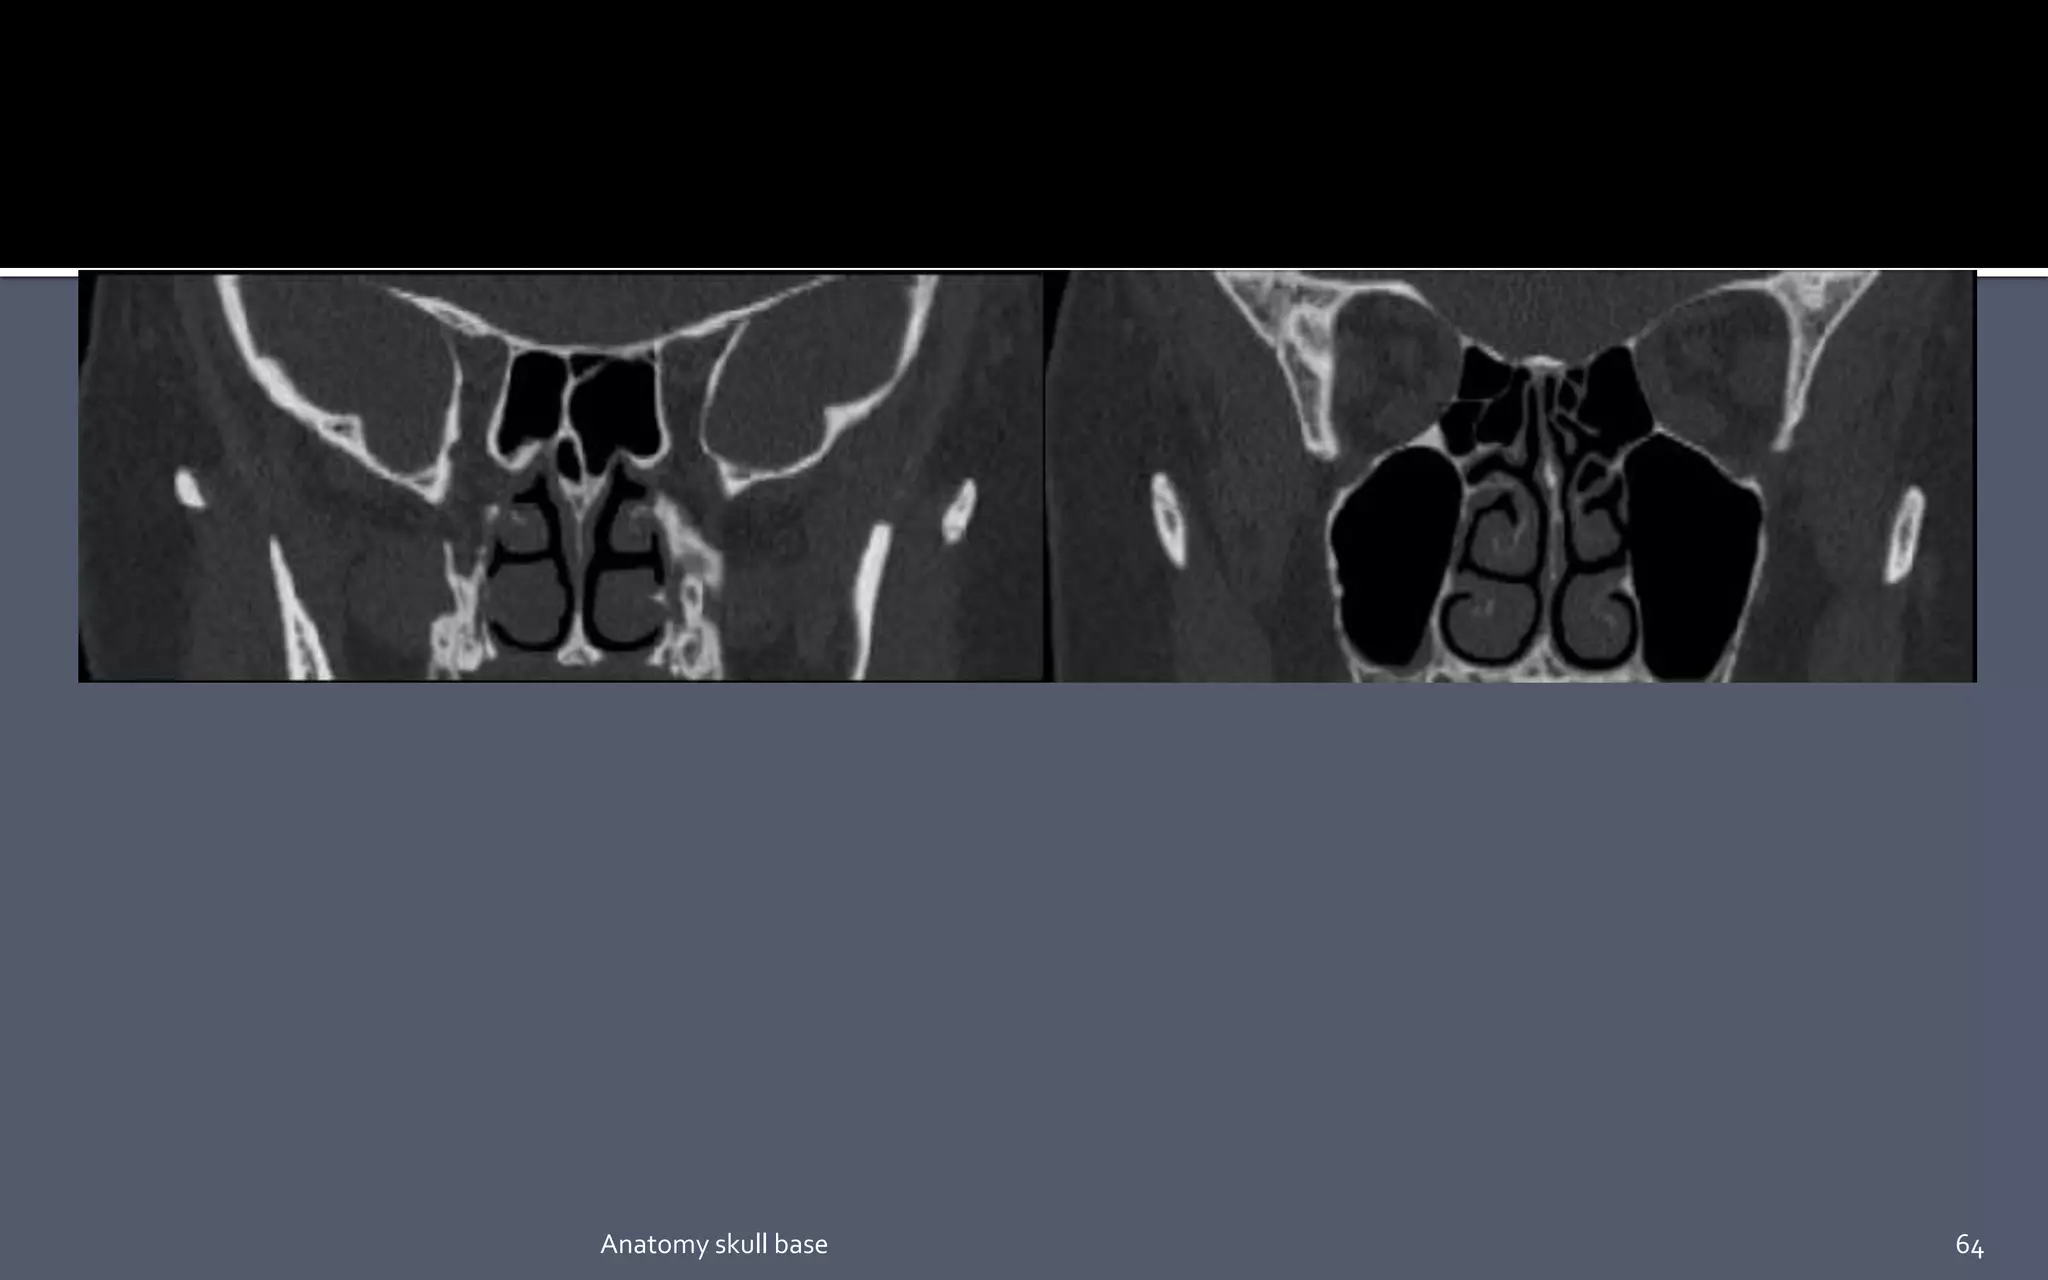

This foramen is best visualized by means of coronal

CT

Is actually acanal in the base of the greater sphenoid wing, is situated just inferior and lateral to the superior orbital fissure. The canal extends obliquely forward and slightly inferiorly, connecting the middle cranial fossa to the pterygopalatine fossa. The canal transmits the maxillary nerve ( V2) the artery of the foramen Rotundum and emissary veins. This foramen is best visualized by means of coronal CT 36Anatomy skull base